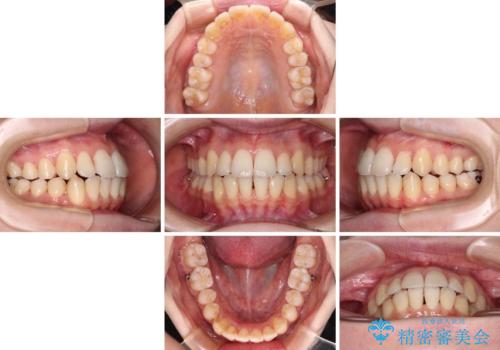

- 前歯の突出感とクロスバイトが気になり、インビザラインによる矯正治療を希望して来院された患者様です。

インビザラインで歯列を移動する前に、上顎前歯をワイヤー矯正で整え、その後上下歯列をインビザラインにて矯正治療を行うこととしました。